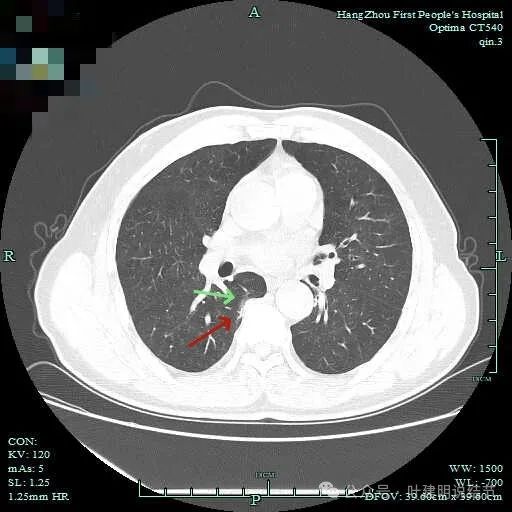

次病灶连续层面观察:

紧贴脊柱处混合密度,趴在脊柱上,这不像结节状。

但有小血管似的,磨玻璃部分界限较清。但此类异常影像在正常人的CT上也挺常见。

密度较高,确实像血管进入。但病灶片状,趴在脊柱上。

此层显得更呈小片状了。

与脊柱间似乎有间隙在,另见微小血管进入这条索状的偏高密度影处。

有细小血管进入,但说不上异常增粗。病灶仍是小片状,条状。

磨玻璃成分密度淡且界欠清,整体就是条索状弯曲的。

上图见细毛刺明显。

病灶实性伴细毛刺,与脊柱间有间隙在。

病仍明显,从上到下,觉得应该是成片的。

表面不平毛刺,实性密度为主。

微小血管有,但无异常增粗。

病灶实性,边缘不光滑。

实性密度,片状,条状。

病灶实性,缺乏膨胀性。

上图呈结节状,表面不平,有少许磨玻璃成分。

结节状,密度高,边缘欠光滑。

与脊柱之间有间隙,表面有细毛刺。

表面不平,似有细支气管截断征。

边缘不平毛糙。

像慢性炎似的。

瘤肺边界欠清。

边缘区淡磨玻璃密度。